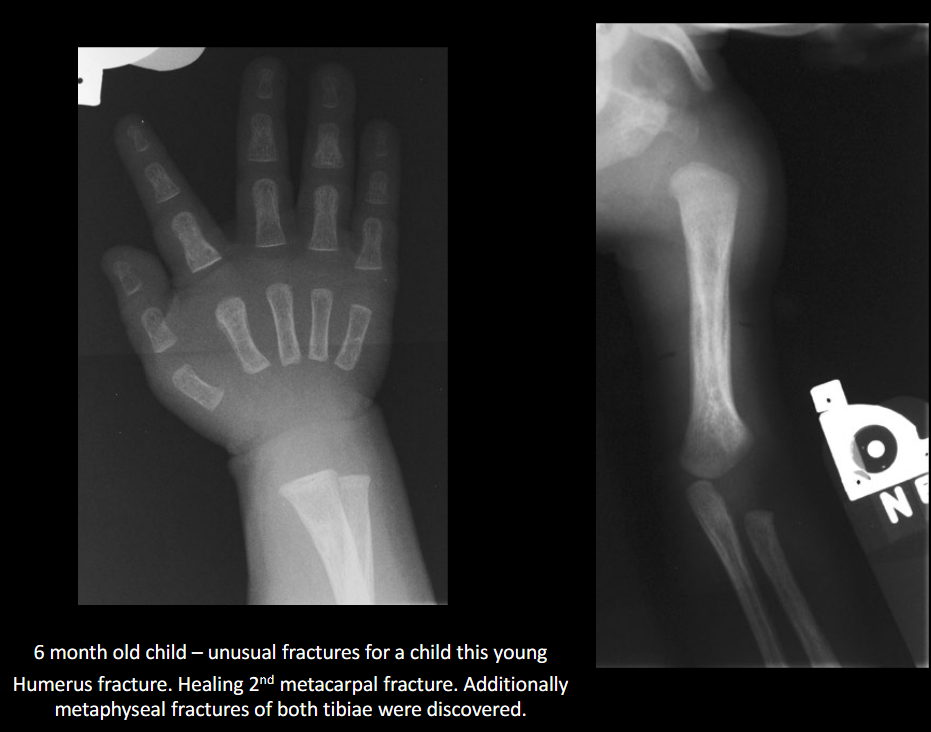

Define NAI.

Non-accidental injury/trauma; deliberate physical harm to a child.

Classic metaphyseal injury in NAI?

Corner/bucket-handle fracture.

Preferred initial imaging in suspected NAI?

Skeletal survey (not a ‘babygram’).